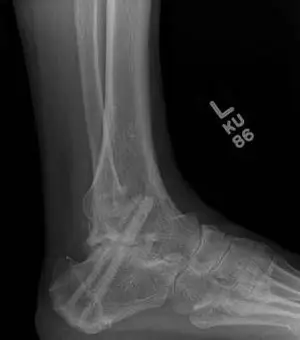

Ankle joint replacements are a reserved procedure for patients who meet certain criteria for functionality involving age, medical conditions, level of arthritis, and activity level, amongst others. The level of arthritis is typically severe and dibilitating as demonstrated in the x-ray image below. This person had a severe ankle fracture many years ago that was surgically repaired and later developed limiting arthritis to the point where they could no longer use their ankle because of pain. There is absence of joint space at the ankle joint along with remodeling of the bones around the ankle due to degeneration of the joint. The abnormal appearance of the thin bone called the fibula is a result of not fixing this bone when the patient had the original surgery.  This is referred to as malunion.

These are pics of the fusion prior to takedown